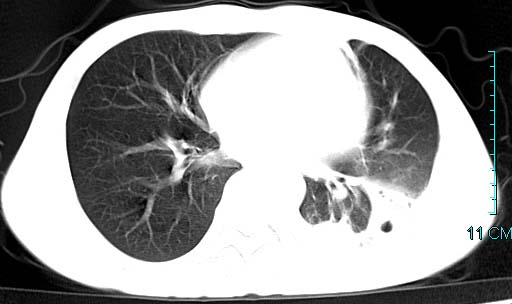

以下是引用qian在2006-3-28 14:32:00的发言:[br]左肺下叶大片状阴影,密度不均,见有条片影和空洞及气液平,少量胸腔积液伴有胸膜增厚,从图像看积液密度比水的密度高,结合病史,考虑左下肺化脓性炎症伴有脓胸。

以下是引用wawaquan在2006-3-28 22:25:00的发言:[br]左上肺舌段多发斑片影。结合“男24y咳嗽咳痰气促伴高热(38.5--39.5)20多天”及穿刺史,[br]考虑1 左下肺化脓性炎症;2脓胸。

以下是引用乡医在2006-3-28 18:37:00的发言:[br]左侧多发液气平面结合患者男24y咳嗽咳痰气促伴高热(38.5--39.5)20多天,查胸水:ldh239.3,总蛋白59.19,tb-ab阴性,利凡它试验+,红c2.7*109,白c1.08*109,分类淋巴92%分叶8%,考虑1脓胸2肺隔离征感染